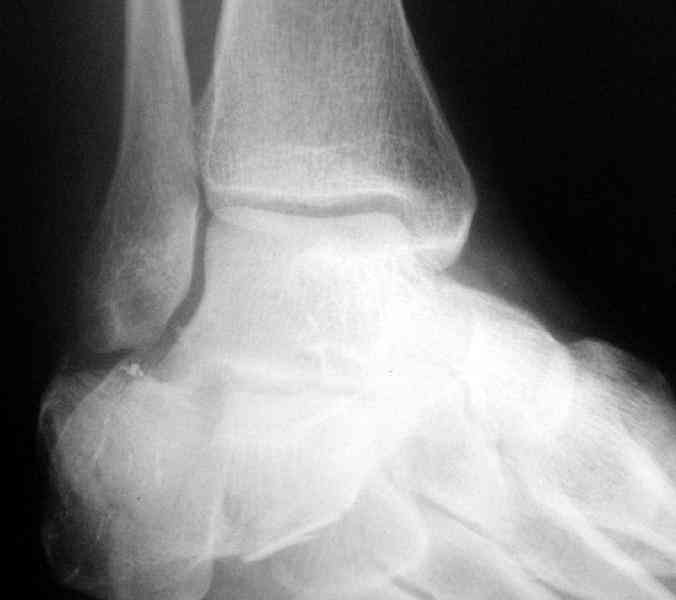

Its a comminuted one.

I would have a CT prior 2 surgery(If u have to postpone a surgery for it - I would operate without one)

I myself would reduce it with EX-FIX and depending on the result would consider a plate on the table.

MOST OF MY COLLEGUES WOULD OPEN IT LATERALLY( a flap) and having a proper reduction would put a plate.

Сустав похоже интактен, киста под вопросом,даже при наличии опыта остесинтеза пластиной, в данном случае выведение правильного угла и фиксация спицами более чем достаточно, да и намного спокойнее сон у хируга.

Перелом безусловно внутрисуставной. Киста-не киста принципиального значения не имеет.